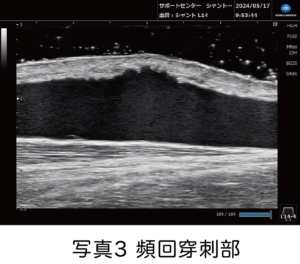

そのほかにシャントエコーチームが行っているシャント管理として、同じ部位に針を刺し続けている「頻回穿刺部(写真3)」を超音波診断装置で患者さまといっしょに血管壁の状態を確認して、穿刺部位を順繰りに変えていく必要性について、直接お伝えすることも行っております。